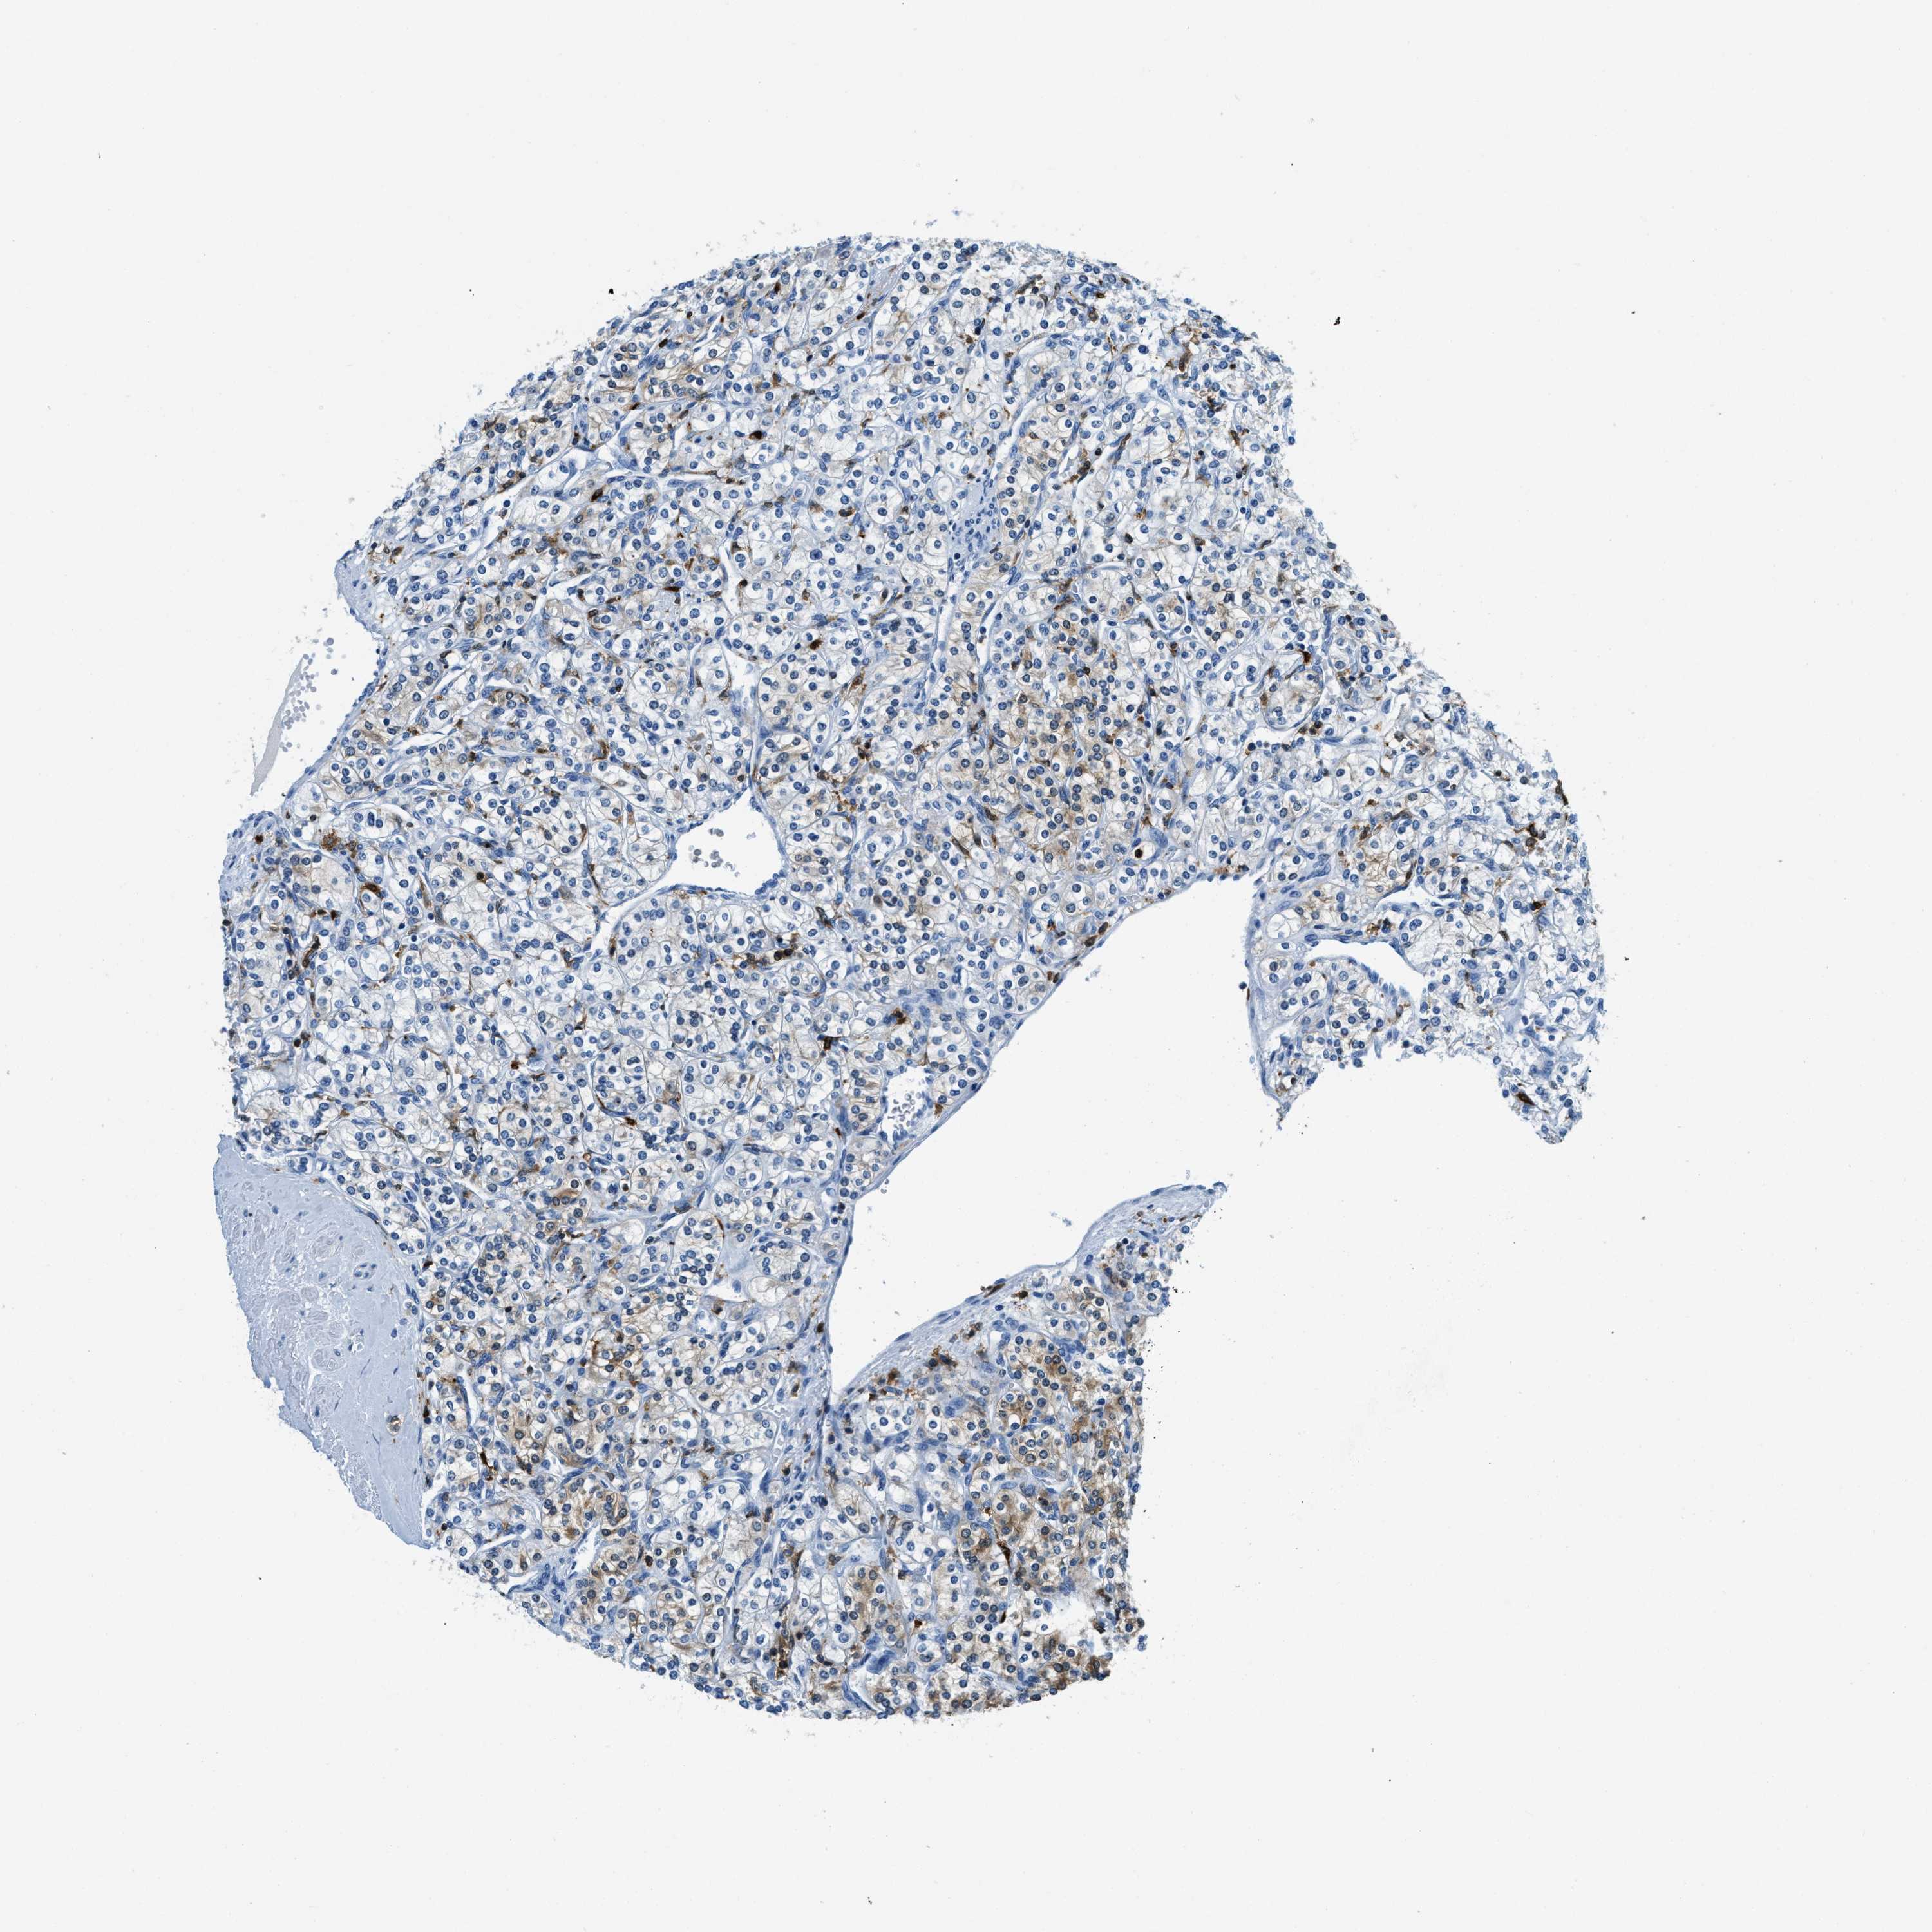

KIDNEY RENAL CLEAR CELL CARCINOMA (VALIDATION) - Interactive survival scatter ploti

The Survival Scatter plot shows the clinical status (i.e. dead or alive) for all individuals in the patient cohort, based on the same data that underlies the corresponding Kaplan-Meier plots. Patients that are alive at last time for follow-up are shown in blue and patients who have died during the study are shown in red.

The x-axis shows the expression levels (FPKM) of the investigated gene in the tumor tissue at the time of diagnosis. The y-axis shows the follow-up time after diagnosis (years). Both axes are complimented with kernel density curves demonstrating the data density over the axes. The top density plot shows the expression levels (FPKM) distribution among dead (red) and alive patients (blue). The right density plot shows the data density of the survived years of dead patients with high and low expression levels respectively, stratified using the cutoff indicated by the vertical dashed line through the Survival Scatter plot. This cutoff is automatically defined based on the FPKM cutoff that minimizes the p-score. The cutoff can be changed by dragging the vertical line or by entering a cutoff value in the square labeled "Current cut-off".

Under the Survival Scatter plot the p-score landscape (black curve; left axis) is shown together with dead median separation (red curve; right axis). Dead median separation is the difference in median mRNA expression between patients who have died with high and low expression, respectively. It is calculated as follows: median FPKM expression of dead patients with high expression - median FPKM expression of dead patients with low expression. This is intended to aid the user in visually exploring custom cutoffs and the associated p-scores and dead median separation.

Individual patient data is displayed and can be filtered by clicking on one or more of the category buttons on the top of the page. Categories describing expression level and patient information include: high, low, alive, dead, female, male and tumor stages. The scale of the x-axis can be toggled between linear and log-scale by clicking on the "x log" button. Mouse-over function shows TCGA ID, patient information and mRNA expression (FPKM) for each patient.

& Survival analysisi

Kaplan-Meier plots summarize results from analysis of correlation between mRNA expression level and patient survival. Patients were divided based on level of expression into one of the two groups "low" (under cut off) or "high" (over cut off). X-axis shows time for survival (years) and y-axis shows the probability of survival, where 1.0 corresponds to 100 percent.

CAPG is not prognostic in Kidney Renal Clear Cell Carcinoma (validation)

Best expression cut offi

Based on the FPKM value of each gene, patients were classified into two groups and association between prognosis (survival) and gene expression (FPKM) was examined. The best expression cut-off refers the FPKM value that yields maximal difference with regard to survival between the two groups at the lowest log-rank P-value. Best expression cut-off was selected based on survival analysis .

When clicking on this number, the vertical dashed line indicating cut-off, the interactive survival plot, and the Kaplan-Meier curve will be adjusted to show results based on the best expression cut-off.

: 291.4

P scorei

Log-rank P value for Kaplan-Meier plot showing results from analysis of correlation between mRNA expression level and patient survival.

N/A

5-year survival highi

5-year survival for patients with higher expression than the expression cutoff.

For melanoma and glioma, 3-year survival is shown.

5-year survival lowi

5-year survival for patients with lower expression than the expression cutoff.

TCGA RNA samplesi

RNA-seq data is reported as average FPKM (number Fragments Per Kilobase of exon per Million reads), generated by the The Cancer Genome Atlas (TCGA) .

Normal distribution across the dataset is visualized with box plots, shown as median and 25th and 75th percentiles. Points are displayed as outliers if they are above or below 1.5 times the interquartile range. FPKM values of the individual samples are presented next to the box plot.

Average pTPM 232.1

Number of samples 100